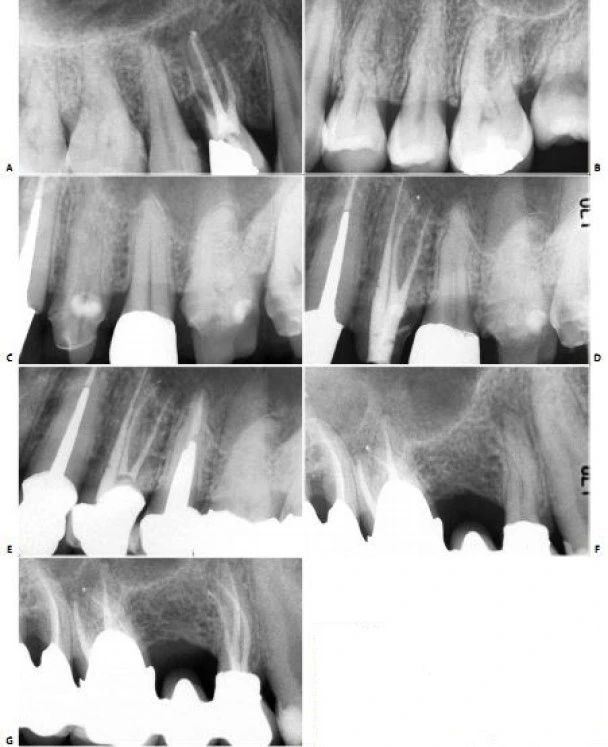

Hình 11.36. A. Phim trong lúc điều trị ở răng #21. B. 12 tháng sau.Chú ý hình ảnh sự lành thương, ba ống tủy phụ đã được trám, 1 ở gần chóp và 2 cái còn lại ở 1/3 giữa và đều ở phía gần. C. Răng #21 với một ống tủy phụ lớn ở 1/3 chóp. Ống tủy phụ ở phía gần và tạo một góc 900 với ống tủy chính. D. Răng #11 với ống tủy phụ nằm gần lỗ chóp và 1 cái lớn hơn ở 1/3 giữa phía gần và tạo góc 900 với ống tủy chính.

Hình 5.41. A. Phim X-quang trước điều trị của răng cửa giữa hàm trên bên phải. Lỗ chóp nằm trên cùng một mặt phẳng trên đường đi của tia X: nó có thể đối diện với mặt trong hoặc mặt ngoài. B. Phim X-quang thứ hai chụp theo hướng gần-xa cho thấy đoạn cong đối diện với mặt ngoài. Việc điều trị tủy được hoàn tất, giữ nguyên góc chụp cho phép nhìn thấy được điểm cuối cùng trên X-quang của ống tủy. C. Phim sau điều trị. Lưu ý rằng chỉ với góc chụp này mới thấy được hình ảnh tổn thương nhỏ tại chóp chân răng. D. Phim sau điều trị được chụp theo tiêu chuẩn hình chiếu. Lưu ý rằng vật liệu trám ống tủy dường như bị ngắn đi chừng 2mm và tổn thương cũng đã lành.